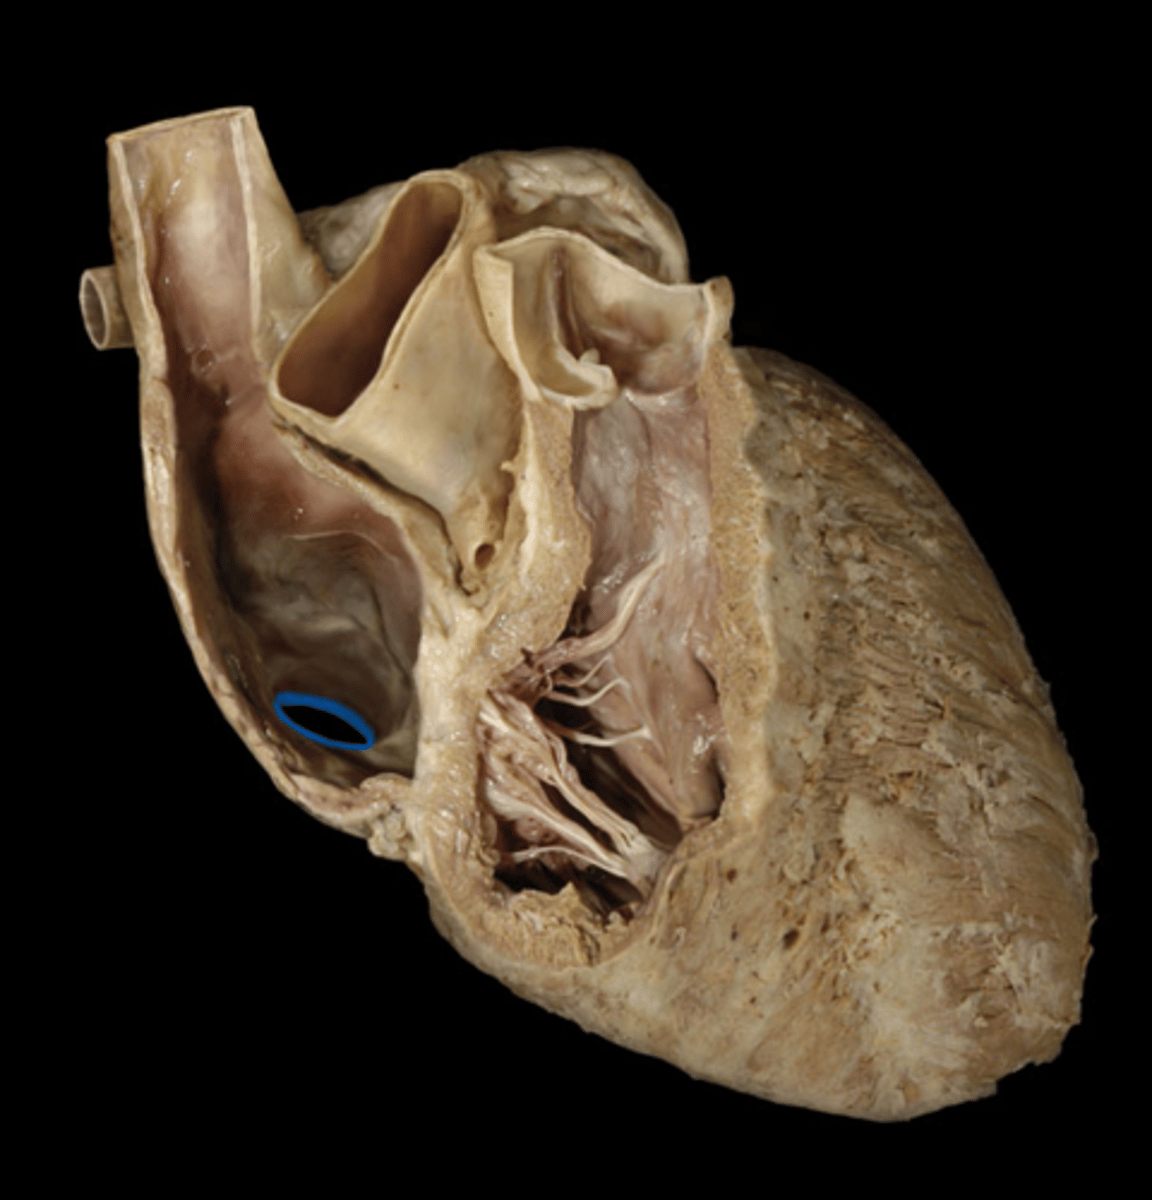

Fossa ovalis

depression

in R atrium, pinto bean buried in R atrium

H5

24

Pectinate muscle

st

stretch jeans on inside of right atrium

webbing on wall of R atrium

Sinus venarum

surface; on inside of right atrium, smooth part, by fossa ovalis

opening of the superior vena cava

opening; tip of probe, posterior side, smaller opening at top

H6

opening of the inferior vena cava

opening; posterior side, end of probe, bottom of shoe, smaller opening at back

Opening of the coronary sinus

opening: Hole below fossa ovalis, just stick tip of probe in